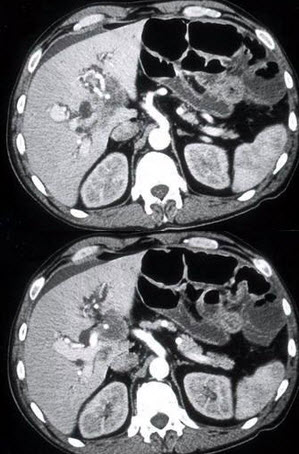

根据所提供的图像,最可能的诊断是( )

A:鹿角状结石

B:肾盂积水

C:肾动静脉畸形

D:黄色肉芽肿性肾盂肾炎

E:肾盂旁囊肿